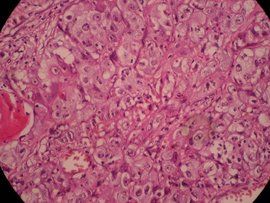

組織病理學

細胞癌鱗狀細胞癌可表現角化、角化珠形成和/或細胞間橋等特徵。這些特徵隨分化程度而表現不同。在分化良好的腫瘤中該特徵表現明顯,而在分化差的腫瘤中僅局部可見。